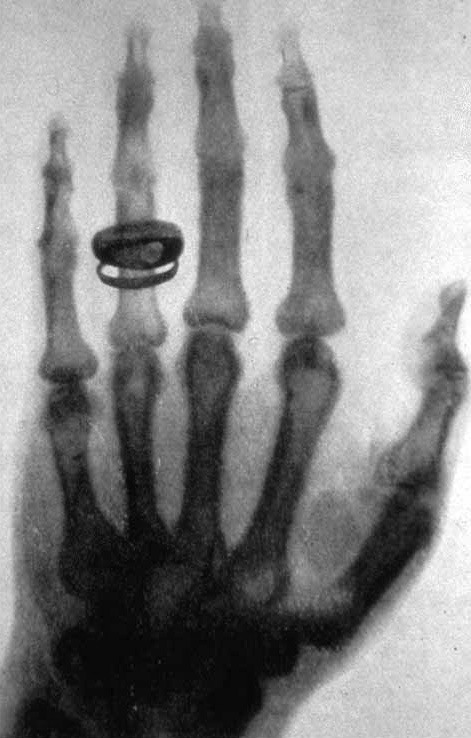

1800년대 후반에서 1900년대 초반에는 물리와 화학에서 중요한 발견이 이루어진 시기입니다. 멘델레예프의 주기율표에 들어가는 여러 가지 원소가 발견되었고, 물질 내부의 구성 요소들이 발견되었습니다. 오늘날 질병 치료에 없어서는 안 되는 역할을 하는 X선이나 여러 가지 방사선도 이 시기에 발견되었습니다. 그 시작을 알린 사람은 독일의 물리학자 빌헬름 뢴트겐(1845~1923)입니다. 1895년 그때까지 알려지지 않아 이름을 붙일 수 없었던 광선을 발견하고 ‘X선’이라 했습니다. 뢴트겐은 이 공로로 1901년 최초의 노벨 물리학상을 수상했습니다. 1896년에는 프랑스의 물리학자 앙리 베크렐(1852~1908)이 우라늄염이라는 광물에서 X선과 다른 광선이 나온다는 사실을 발견하고 ‘베크렐선’이라고 이름을 붙였습니다.

X-ray_by_Wilhelm_Röntgen_of_Albert_von_Kölliker's_hand_-_18960123-02.jpg 뢴트겐이 찍은 손가락의 X선 사진 Ⓒ Public domain(Wikipedia)